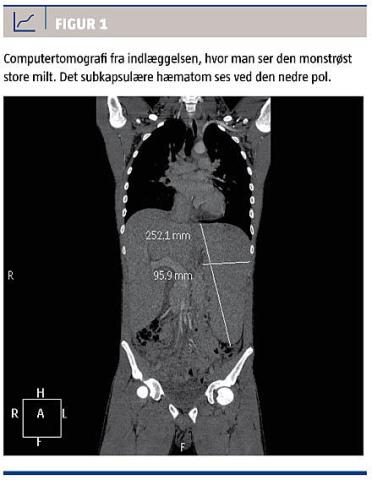

Objektivt fandt man ved indlæggelsen: ikterus, febrilia med en temperatur på 40 °C, takykardi med en puls på 131 slag/min, hypotension med et blodtryk på 108/61 mmHg. Abdomen var øm og spændt, men uden peritonealreaktion, der var hepato- og splenomegali til ca. tre fingre under kurvaturerne og en tonsilsvulst med belægninger. Biokemisk fandt man svær leverpåvirkning med okklusivt mønster, let påvirkede infektionsparametre og et hæmoglobinniveau på 4,4 mmol/l. Patienten blev indlagt primært til

observation på infektionsmedicinsk afdeling, men blev efter kort tid overflyttet til intensivafdelingen i organkirurgisk regi på grund af en computertomografi (CT)-verificeret monstrøst forstørret milt (25 × 10 cm) med ledsagende subkapsulært hæmatom

(Figur 1). Da han var hæmodynamisk stabil, blev han behandlet konservativt med tæt observation og roligt regime i form af sengeleje i den første uge. Efter en uges observation, hvor patienten havde været stabil, blev der udført en CT-kontrol, som viste stationære forhold omkring milten. Patienten begyndte gradvist at blive mobiliseret og blev flyttet tilbage til stamafdelingen. Han blev udskrevet til ambulante kontroller efter 12 dage, stadig stabil og med fint stigende hæmoglobinniveau.